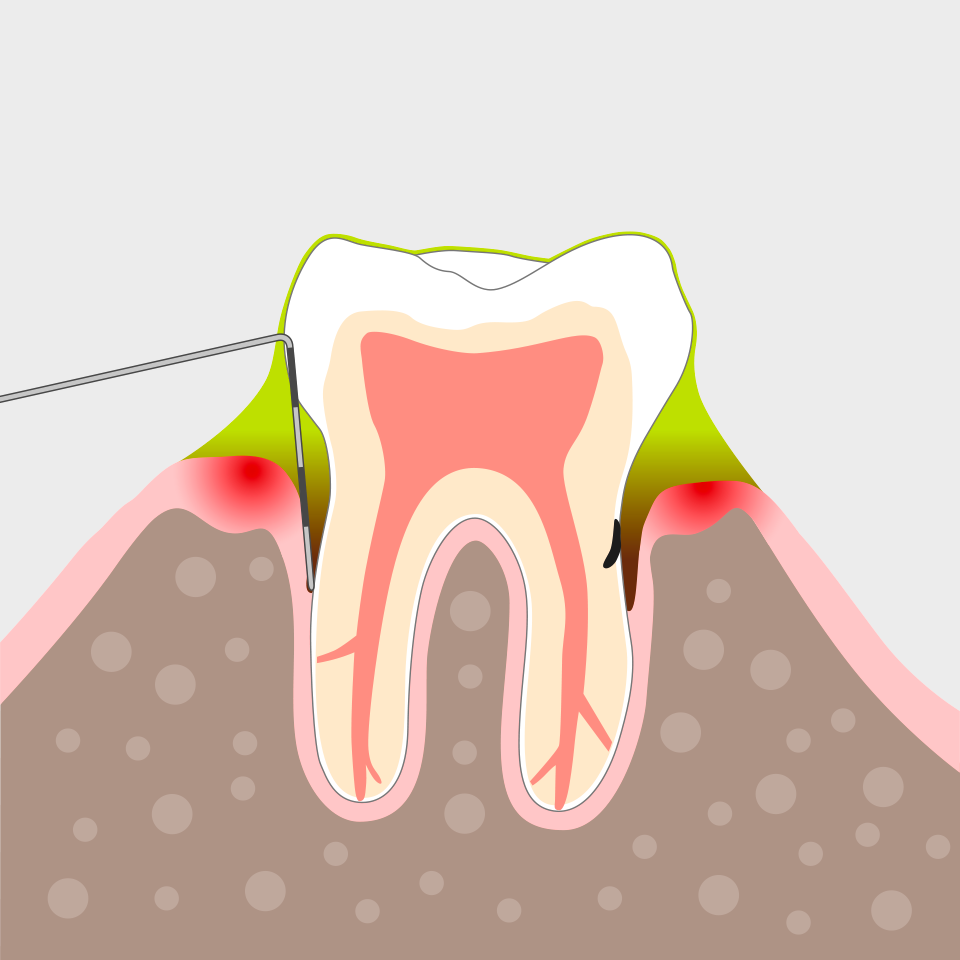

Befundung und Diagnose

Zunächst entfernen wir den Zahnbelag oberhalb des Zahnfleischsaumes (Gingiva) …